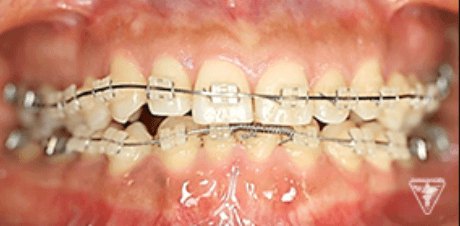

治療過程①